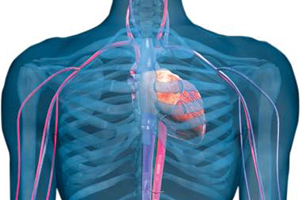

Sistema cardiovascular

En conjunto, el corazón, la sangre y los vasos sanguíneos conforman el sistema cardiovascular.

El corazón

Es un órgano muscular hueco, ubicado en la zona conocida como mediastino, espacio que se encuentra en el centro de la caja torácica hacia el lado izquierdo, por detrás del esternón, entre las costillas y los pulmones. Su función principal es impulsar sangre a todo el cuerpo, además de llevar oxígeno y nutrientes a órganos y tejidos.

Vasos sanguineos

El sistema de canalizaciones de nuestro cuerpo está constituido por los vasos sanguíneos, que según su diámetro se clasifican en: arterias, venas y capilares. Por esta estructura de conductos grandes y pequeños, circula la totalidad de nuestra sangre una y otra vez.

Cavidades y válvulas cardíacas

El corazón está compuesto por cuatro cavidades, dos superiores (aurículas) y dos inferiores (ventrículos). Las primeras son las receptoras del corazón y las segundas son las que bombean la sangre.

Además, dentro del corazón hay cuatro válvulas, dos auriculoventriculares (tricúspide y mitral o bicúspide) y dos semilunares (pulmonar y aórtica), que mantienen el flujo unidireccional de la sangre dentro del corazón.